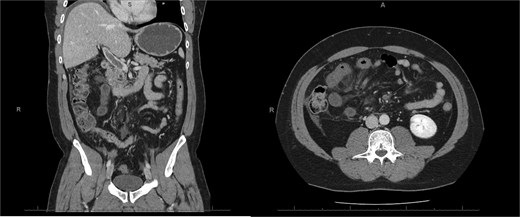

A 76-year-old female with a 3-day history of left upper abdominal pain, vomiting, and haematochezia. Her history included pulmonary embolism, multiple deep vein thromboses, with no ongoing anticoagulation, and an open partial colectomy for complicated diverticulitis a decade earlier. On admission, she was afebrile but tachycardic and showed localized tenderness in the left hypochondrium. Laboratory revealed leucocytosis with a white blood cell count (WBC) of 12 G/L, elevated C-reactive protein (CRP) of 46 mg/L, and hyperlactatemia of 2.6 mmol/l. Enhanced computed tomography (E-CT) revealed jejunal venous ischemia in the left upper quadrant, secondary to extensive porto-mesenteric thrombosis with reduced bowel wall enhancement, distention, and free intraperitoneal fluid (Fig. 1). She was managed conservatively with unfractionated heparin (UFH) with a bolus of 5000 U/l followed by 30 000 U/l/24 h (target INR 0.35–0.7), Piperacillin-Tazobactam, and bowel rest. After 48 h of monitoring in the intensive care unit (ICU), she exhibited marked biological and clinical improvement. E-CT on the third day showed restored bowel wall enhancement and stable porto-mesenteric thrombosis (Fig. 2). She was discharged on therapeutic low molecular weight heparin (LMWH) with enoxaparin sodium 120 mg every 12 h. At the 3-month follow-up, E-CT revealed near-complete thrombus resolution, without intestinal sequelae (Fig. 3).

Follow-up E-CT 72 h after conservative management in the first patient. Dashed arrows show improved viability of the small bowel with bowel wall enhancement. White arrows revealed the stability of the extended porto-mesenteric thrombosis.